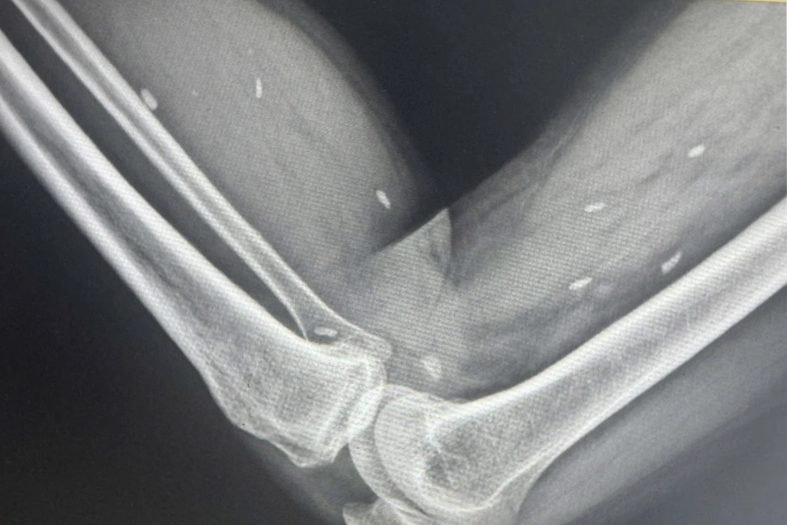

Cụ thể, thời gian thực hiện một quy trình kỹ thuật chẩn đoán hình ảnh được tính từ khi người bệnh bắt đầu thực hiện kỹ thuật đến khi có kết quả chẩn đoán, bao gồm các khâu chuẩn bị, chụp, đọc phim và kết luận. Một số mốc thời gian tham chiếu như: Chụp X-quang xương khớp hoặc phổi, bụng thường quy khoảng 6-12 phút; chụp X-quang dạ dày, đại tràng khoảng 20–30 phút; siêu âm ổ bụng, tuyến giáp khoảng 6-15 phút.